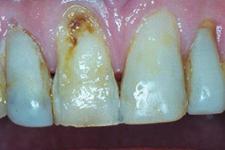

Parodontite moderate

dintii par alungiti datorita retractiei gingivale

pot apare abcese parodontale

halena

mobilitate dentara si diastemizare patologica

pungi parodontale de 4-6 mm

resorbtie osoasa